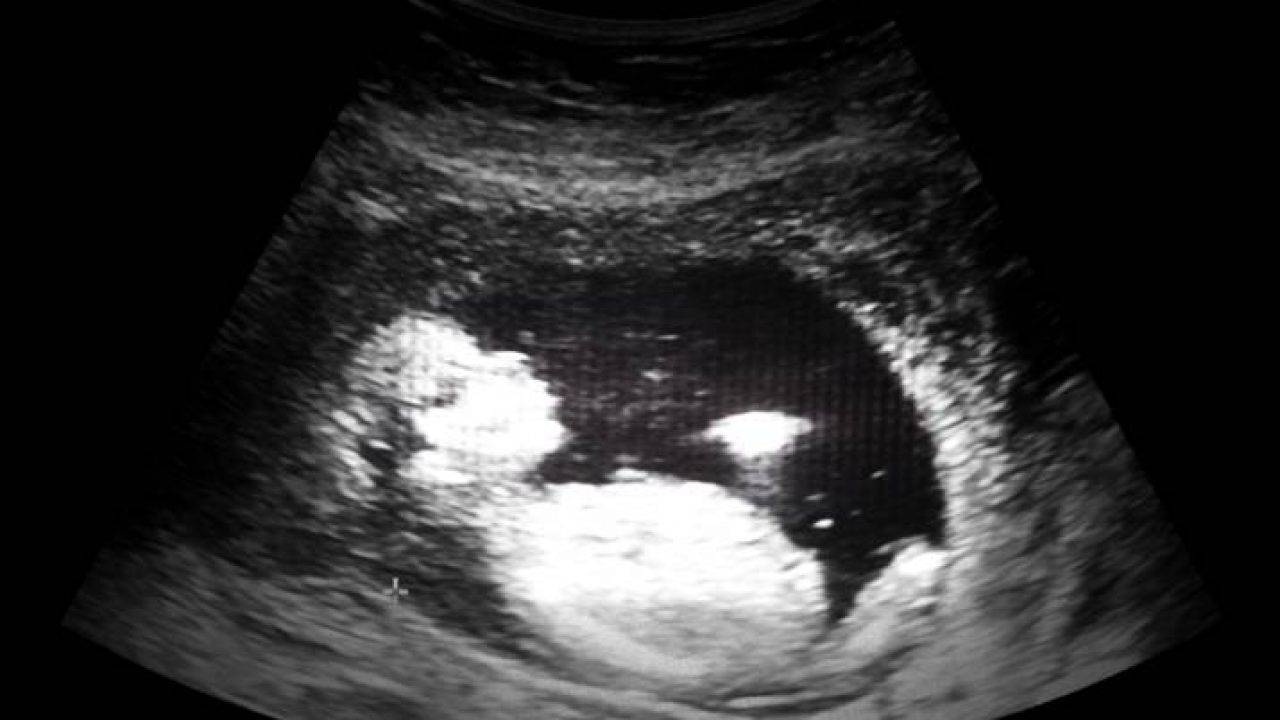

Ecografia Gravidanza A 7 8 Settimane Dr Pietro Agosta Ginecologo Modica Ragusa Dr Pietro Agosta Ginecologo Modica Ragusa

Ecografia 8 Settimana Di Gravidanza Commentata Youtube

Ecografia 8 Settimana Di Gravidanza Bambino E Cordone Ombelicale Youtube

Ecografia Feto 8 Settimane Youtube